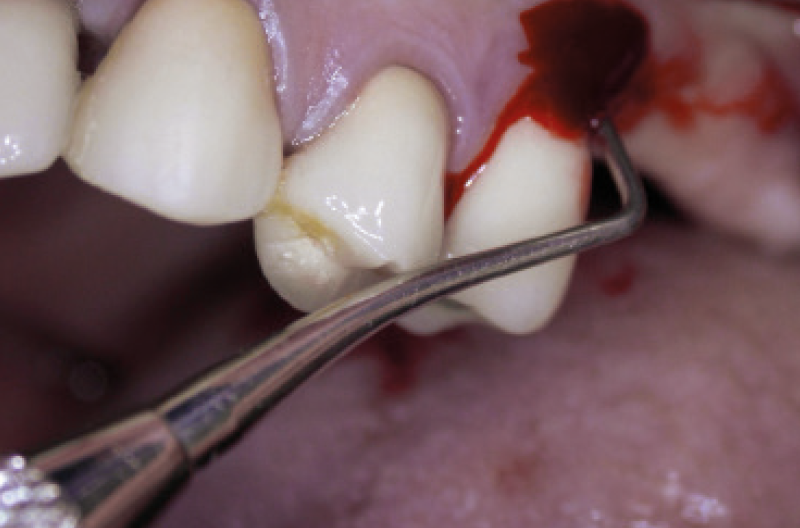

Il caso di seguito presentato riguarda un paziente di 54 anni giunto alla nostra osservazione a fine 2003 con un quadro di fallimento implantoprotesico su due impianti in sede 15 e 16 inseriti nel 2001 presso studio della zona. È un paziente a rischio perché parodontale, fumatore, diabetico, igienicamente non motivato. La protesi implantare è mobile, la gengiva dolente e secernente pus. L’unico piano di trattamento possibile è la rimozione degli impianti e la decontaminazione del sito tramite curettage in copertura antibiotica (Figg. 13-15).

- Fig. 14 – Segni di flogosi mucosa perimplantare. Mobilità protesica. Dolore. Sono espressioni cliniche di perimplantite

- Fig. 15 – La protesi implanto-supportata viene rimossa. La superficie implantare è contaminata, l’osso è andato perduto e sostituito da tessuto di granulazione